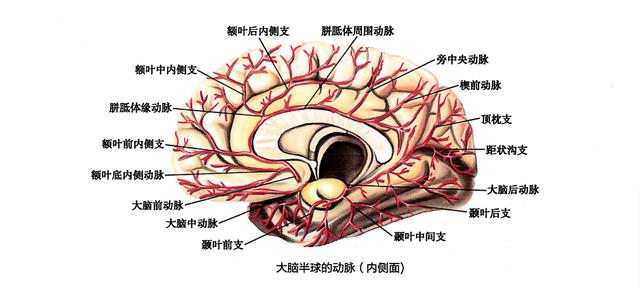

脳への血液供給は、主に首の前にある内頸動脈と首の後ろにある椎骨動脈という2本の血管から行われている。この2本が脳を正常に機能させるための生命線である。

内頸動脈は主に脳の最初の3分の2を供給している。

椎骨動脈は主に脳の後部3分の1と小脳に供給している。

脳の各部分は異なる部分に分かれているため、2つの血管病変によって引き起こされる症状は異なる。

内頸動脈への血液供給が不十分な患者にみられる症状には、以下のようなものがある。頭痛、めまい(全身がだるく、やる気が出ない)、記憶力の低下、睡眠不足、顔のしびれ、体がしびれる感じ、手足の脱力感、目がかすみやすい、失神。

椎骨動脈からの血液供給不足症状としては、耳鳴り、難聴、めまい(めまいとは異なり、周囲で物が回転しているような感覚)、嘔吐、ふらつき、歩行不安定、ふらつき、ふらつきなどがある。

脳への血液供給は内頸動脈と椎骨動脈から行われ、虚血の症状はさまざまである。

I. 内頸動脈への血液供給不足

主な症状は視覚障害または大脳半球の病変である。

例えば、左側の虚血の場合、視覚障害は左目、運動・感覚障害(または片麻痺)は右手または右足に現れる。両方の症状が同時に現れるケースは少ないが、ほとんどの場合は別々に現れる。

一過性の単眼失明や一過性の失神が最も一般的である。失明とは、視野の明暗が徐々に減少(または増加)し、片眼の完全な無痛失明に至るものである。また、不完全な視野、視界の完全なぼやけ、視界の灰色または明るいぼやけとして現れることもあります。失明を見逃しやすいため、眼科医に相談する人もいる。

椎骨動脈への血液供給不足

症状はさまざまで、めまい、複視、構音障害、両側顔面しびれ、運動失調、片側または両側の手足の脱力感やしびれなどがしばしばみられる。

あまり一般的でない症状としては、片麻痺、頭鳴りや耳鳴り、頭痛やその他の特異な頭部感覚、嘔吐、噯気、傾斜感覚、記憶喪失、行動障害、眠気、聴力障害、難聴、片側の手足の痙攣、幻覚、共役しない眼球などがある。